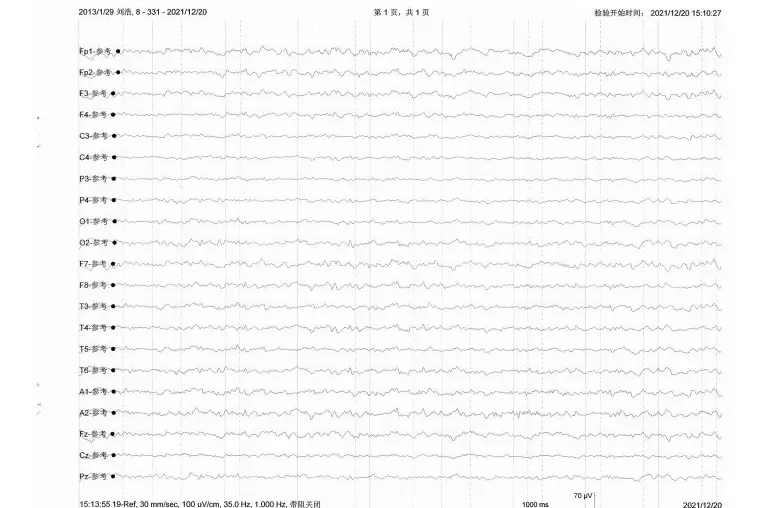

The child experienced hypoxia and ischemia at birth. At the age of 1, it was noticed that the child couldn't sit or walk independently. After seeking medical attention, the diagnosis was cerebral palsy, and no specific treatment was administered. The child has been undergoing self-rehabilitation since returning home. Currently, the child has a slightly diminished intellectual capacity, unclear speech with 5-6 syllables, and increased muscle tone in all limbs, particularly pronounced in the left upper limb and right lower limb. When lifted, the right foot shows inward turning. To further diagnose and treat the condition, the child has been admitted to our hospital. Since the onset of the condition, the child has maintained clear consciousness, good mental well-being, normal eating and sleeping habits, and regular bowel and bladder function. There is no significant change in weight. The child is unable to walk independently and shows no signs of leg swelling.

After admission, a comprehensive examination was conducted, ruling out any surgical contraindications. Due to symptoms of cerebral palsy, the patient underwent a robot-assisted stereotactic brain surgery on December 23, 2021, under combined inhalation anesthesia. The surgical procedure went smoothly, with approximately 3 milliliters of blood loss during the operation. Postoperatively, the surgical site was locally sutured and subjected to pressure dressing. A follow-up head CT scan revealed no apparent bleeding, confirming accurate targeting of the surgical site. The patient returned to the ward smoothly after the surgery and received routine intravenous fluids, oxygen supplementation, and cardiac monitoring. No adverse reactions or complications have occurred to date.